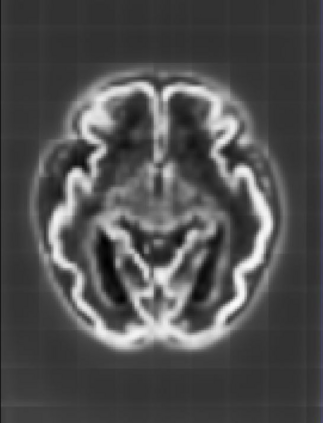

Fetal cortical plate segmentation is essential in quantitative analysis of fetal brain maturation and cortical folding. Manual segmentation of the cortical plate, or manual refinement of automatic segmentations is tedious and time-consuming. Automatic segmentation of the cortical plate, on the other hand, is challenged by the relatively low resolution of the reconstructed fetal brain MRI scans compared to the thin structure of the cortical plate, partial voluming, and the wide range of variations in the morphology of the cortical plate as the brain matures during gestation. To reduce the burden of manual refinement of segmentations, we have developed a new and powerful deep learning segmentation method. Our method exploits new deep attentive modules with mixed kernel convolutions within a fully convolutional neural network architecture that utilizes deep supervision and residual connections. We evaluated our method quantitatively based on several performance measures and expert evaluations. Results show that our method outperforms several state-of-the-art deep models for segmentation, as well as a state-of-the-art multi-atlas segmentation technique. We achieved average Dice similarity coefficient of 0.87, average Hausdorff distance of 0.96 mm, and average symmetric surface difference of 0.28 mm on reconstructed fetal brain MRI scans of fetuses scanned in the gestational age range of 16 to 39 weeks. With a computation time of less than 1 minute per fetal brain, our method can facilitate and accelerate large-scale studies on normal and altered fetal brain cortical maturation and folding.